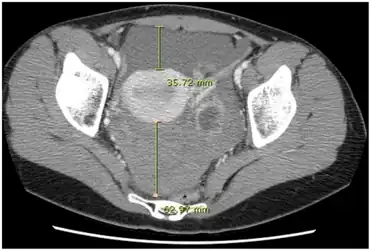

| CT quantification of hemoperitoneum. | |